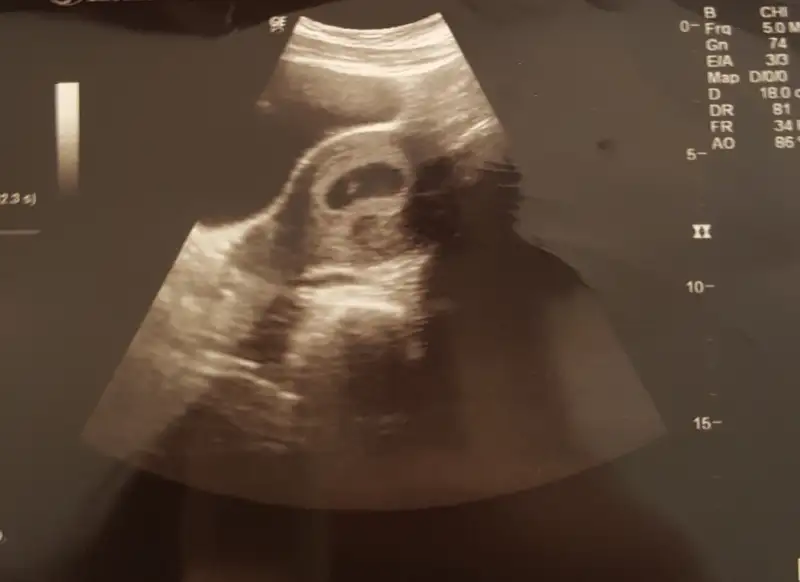

Merhaba bir de bunu yorumlayabilir misiniz plesanta yönüne göre 6 hafta 4 günlükUltrason vajinalse erkek abdominalse kız gibi

kızMerhaba bir de bunu yorumlayabilir misiniz plesanta yönüne göre 6 hafta 4 günlük

Vajinalse erkek gibi abdominalse kiz gibiMerhaba bir de bunu yorumlayabilir misiniz plesanta yönüne göre 6 hafta 4 günlük